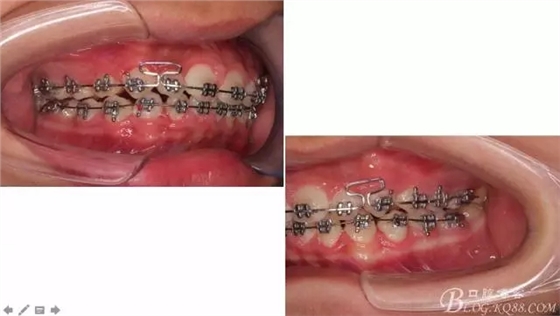

佩戴三個月的FR2, 效果奇佳!前牙基本達到淺覆蓋,淺覆合!接下來進入二期直絲弓固定正畸,排齊階段!

接下來盡管配合些雙側后牙對角牽引,咬合關系依,不盡人意。

下頜配合多曲方絲,三角牽引,調整咬合。

中線不齊,咋辦?繼續(xù)哄哄患者配合,2牽+斜牽。

努力沒有白費,中線基本對齊!